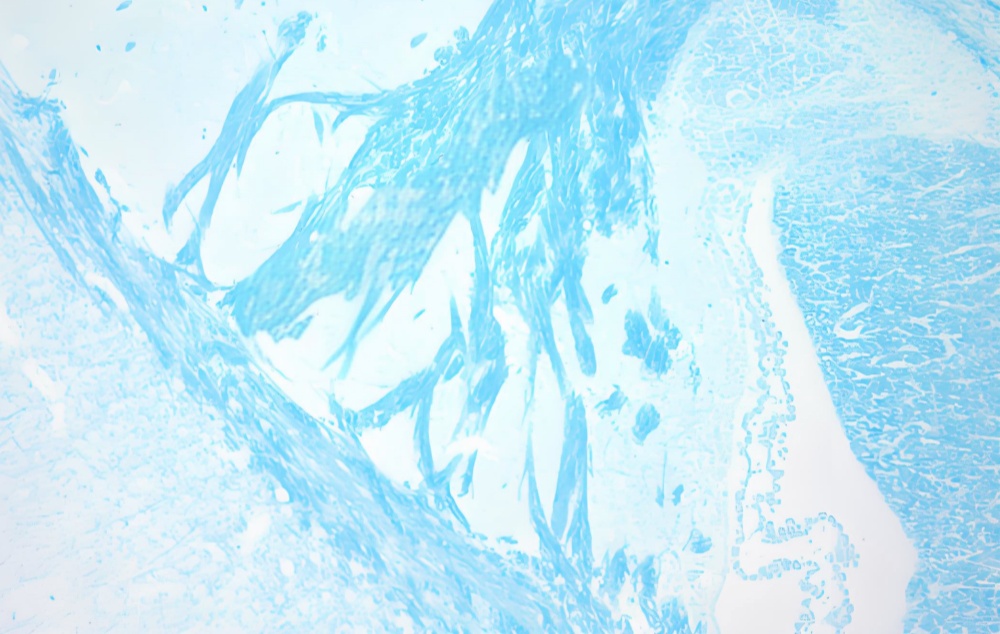

LFB染色(髓鞘)

LFB(Luxol Fast Blue)染色是一种经典的髓鞘(Myelin)特异性染色技术,通过铜酞菁染料与髓鞘磷脂的极性基团结合,使神经纤维的髓鞘结构呈现鲜明的蓝绿色,而神经元胞体及背景组织保持浅染或无色。该技术具有高度特异性和优异的分辨率,可清晰显示中枢及周围神经系统的髓鞘完整性,广泛应用于多发性硬化症、脊髓损伤及周围神经病变的病理诊断与研究。其操作稳定、结果可靠,是神经病理学评估脱髓鞘疾病的核心工具。

LFB染色的原理基于劳克坚牢蓝与髓鞘磷脂的化学结合。LFB在酒精溶液中与髓鞘中的磷脂特异性结合,随后通过分色步骤(如碳酸锂溶液和梯度酒精处理)去除非特异性染色,最终使髓鞘呈现亮蓝色,背景清晰。部分实验方案会结合复染(如焦油紫或苏木素-伊红)以增强细胞核或神经元结构的对比度。

结果判读

髓鞘:亮蓝色或鲜蓝色。

背景:无色至浅蓝色,复染后细胞核呈红色或深蓝色。